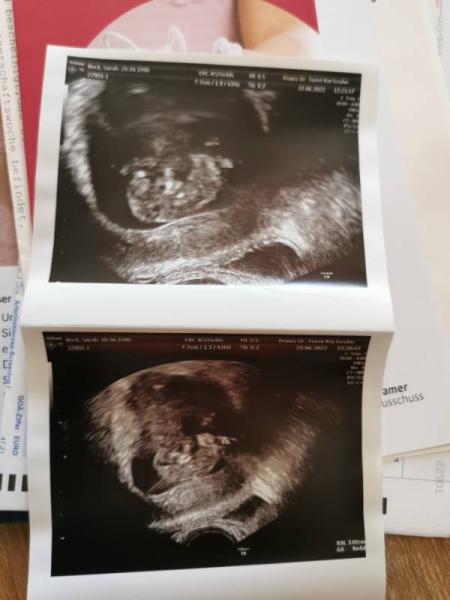

Huhu ihr lieben, Gestern hatte ich wieder einen Termin bei meiner Frauenärztin und es sieht alles supi aus :) Nun sitze ich hier am Ultraschallbild und finde irgendwie schaut das komisch aus. Bei meiner Tochter war dieser Schatten (oder was auch immer) nie zu sehen. Vielleicht habt ihr ja eine Ahnung was das sein könnte oder ob das doch normal ist :) Nächster Termin ist in drei Wochen.

Ich bin da ganz schlecht bei den Bildern, aber die Ärztin hat bestimmt auch alles für richtig und gut befunden. Der "Schatten" kann bei eurem neuen Glück einfach nur durch eine ganz andere Lage sein als bei eurem Mädchen. Es wird alles in Ordnung sein.

Manchmal sehen Ultraschallbilder komisch aus, wenn die Ärztin sagt es ist alles OK, dann würde ich davon ausgehen, dass es so ist :)